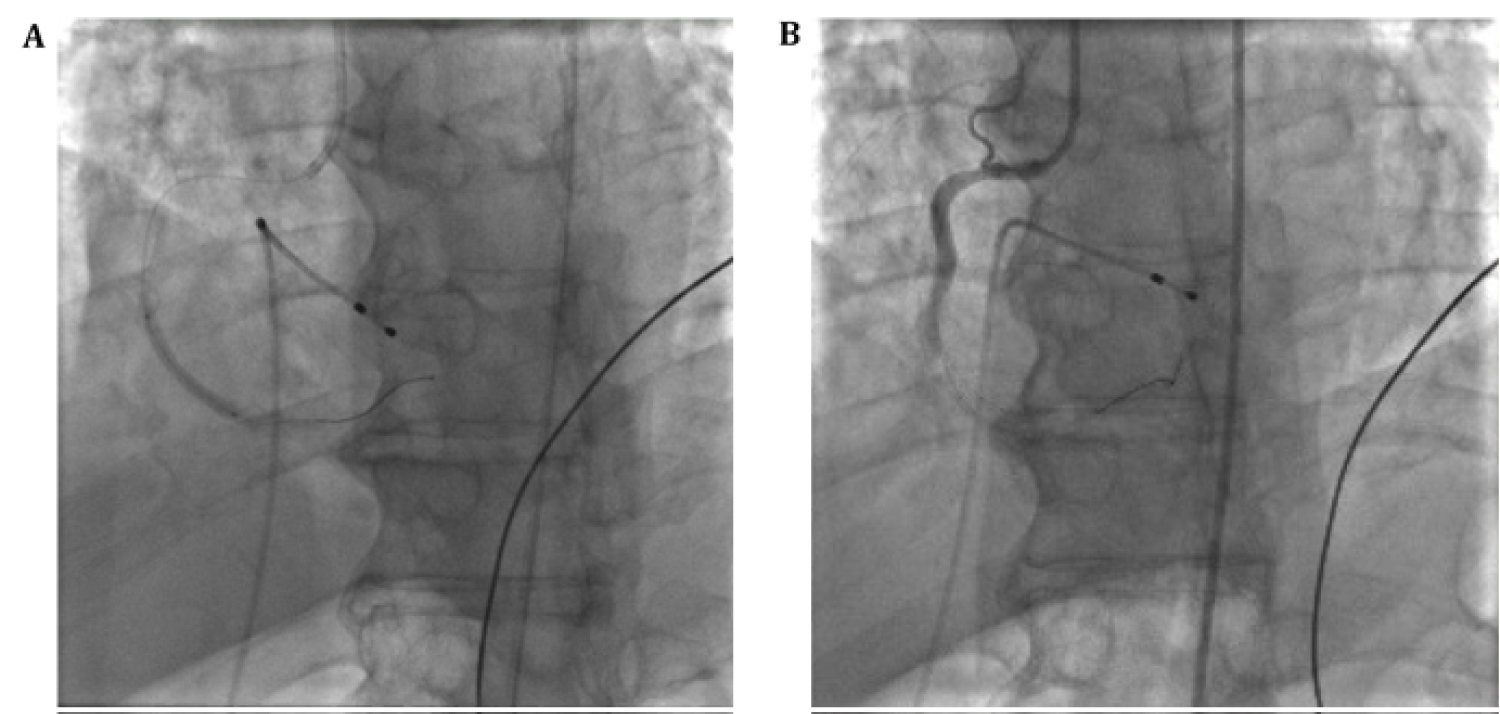

Cardiac catheterization showed 100% mid right coronary artery (RCA) stenosis as well as moderate disease in the left anterior descending artery (LAD) (Figure 2 and Video 1). The decision was made to perform PCI of the RCA lesion; however, despite thrombectomy, balloon angioplasty, stenting, and intracoronary vasodilators and glycoprotein IIb/IIIa inhibitors, there was TIMI flow 0 (Figure 3, Video 2 and Video 3). Intravascular ultrasound was performed to assess stent expansion and the distal coronary vessel. The epicardial vessel visualized distal to the stent was patent with mild atherosclerosis, with no visible edge dissection. It was determined the distal coronary bed could not regain flow due to persistent microvascular thrombus and occlusion. An intra-aortic balloon pump was placed prior to transfer to intensive care unit and an eptifibatide infusion was continued for 18 hours.

Figure 2: (A) Coronary angiography showing mid-RCA 100% occlusion; (B) Moderate LAD disease. View Figure 2